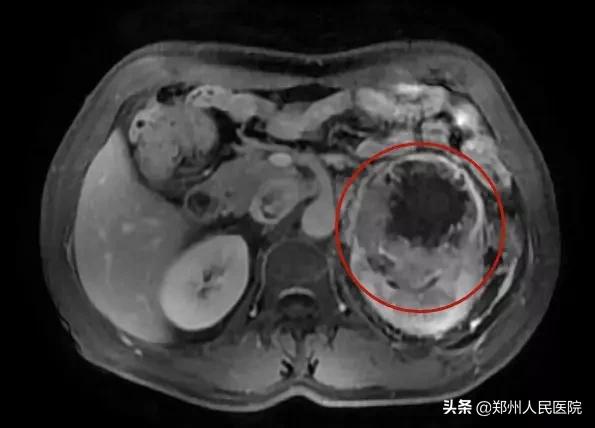

之后老王又因左腰部胀痛不适,在当地医院经过CT检查,发现左肾恶性肿瘤,建议手术治疗。

入院后,老王迅速完善相关检查,经检查最终被确诊为左肾恶性肿瘤伴下腔静脉癌栓形成。

癌栓通俗的说,就是肿瘤转移到了下腔静脉内,相当于肿瘤顺着血管长到了下腔静脉!如果癌细胞顺着静脉往心脏跑,就会在静脉里形成肿瘤的团块,那就是癌栓。

一旦患者发现癌栓,往往病情已经进展到了肾癌晚期。